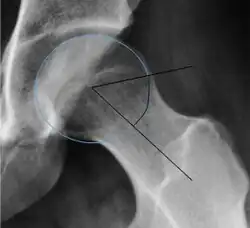

Measurements of impingement on X-ray.[notes 1][20]

Measurement Image Target Normal value

Center-edge angle of Wiberg

The superior-lateral coverage of the femoral head.

• >20° (<55 years old)[notes 2]

• <24° (>55 years old)[notes 2]

• >40° indicates overcoverage

Alpha angle

Measured in 45° Dunn view.

Degree of bulging of the femoral head-neck junction: In normal conditions there is a symmetric concave contour at the junction of the femoral head and neck. Loss of this concavity or bone bulging may lead to cam type impingement. The degree of this deformity can be measured by the alpha angle. Although it can be measured in the cross-lateral view, the 45° Dunn view is considered more sensitive and the frog leg view more specific in determining pathologic values.

• Normal: ≤68° in men, ≤50° in women

• Borderline: 69° to 82° in men, 51° to 56° in women

• Pathological: ≥83° in men and ≥57° in women

Femoral head-neck offset

Measured in cross-lateral view.

Offset of the femoral head with regard to most prominent aspect of the femora neck >10 mm

Offset percentage Femoral head-neck offset related to femoral head diameter >0.18

• less indicates high risk of cam type impingement